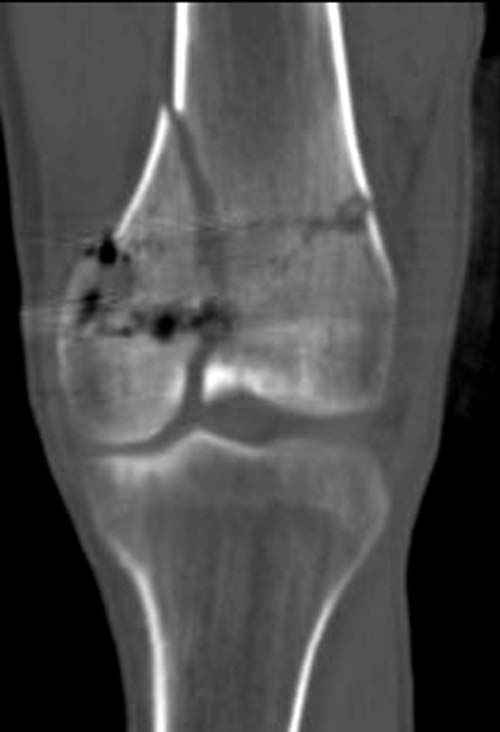

По Густило и Андерсену все high-energy переломы являются III не зависимо от степени повреждения мягких тканей. Plating такого перелома на второй день кажется немного рискованным хотя "победителей не судят". Судя по КТ, медиальный мыщелок стабильный, насколько необходимо было его фиксировать?

Идеальная репозиция?! -На снимочке A-P проeкции видна "зазубрина" по суставной поверхности, латеральный снимок - тоже не идеально.

Множество мелких FB в кости.